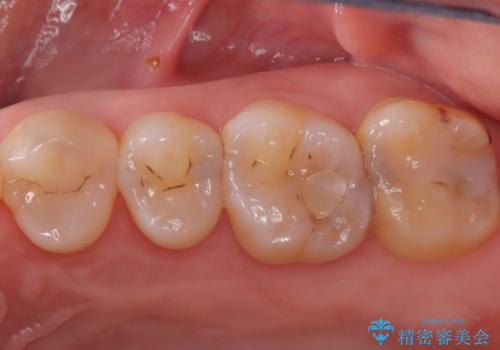

2回で完了した奥歯のセラミック修復

- 奥歯の虫歯治療を主訴にご来院されました。患者様から「できるだけ通院回数を少なく、早く治療を終わらせたい」というご要望があったため、短期間での完了を目指し、セラミックインレー(詰め物)とセラミッククラウン(被せ物)を併用する治療計画を立案しました。治療は精密機器を活用し、2回の来院で最終的なセラミック修復物を装着することを目指します。

今回の治療では、虫歯の大きさや深さに応じて、異なるセラミック修復法を適用しました。

比較的軽度な虫歯には、セラミックインレー(詰め物)で対応し、健全な歯質を最大限に残しました。

進行した虫歯や歯の強度が低下している歯には、セラミッククラウン(被せ物)を選択し、歯全体を保護することで破折を防ぎました。